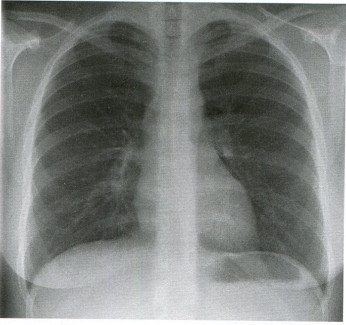

청진 및 기본진찰상 큰 이상소견은 없었으나 반복되는 기침 원인 확인 및 늑막염 및 폐렴 등의 가능성을 감별하기 위하여 흉부 엑스레이를 촬영하였으며 이상소견은 없으며 투약 후 경과를 보았습니다.